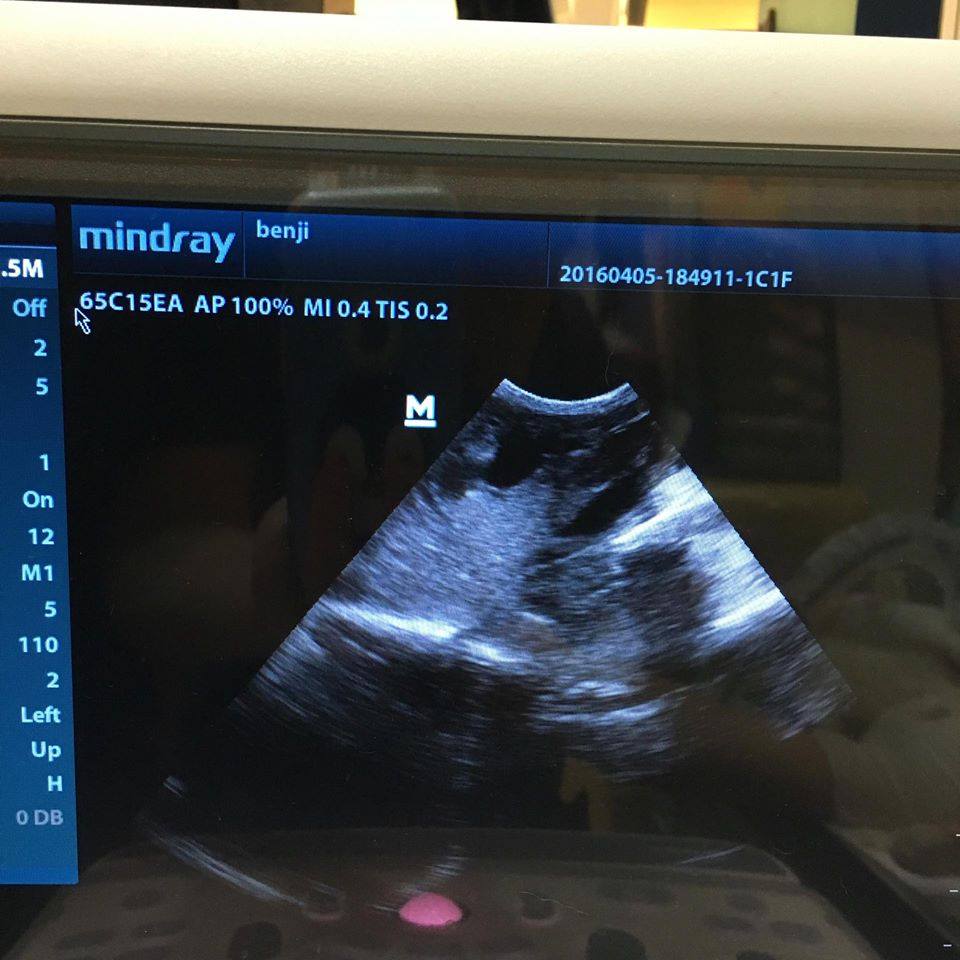

送醫檢查後,

透過X光、超音波觀察,

阿水的腫瘤已經壓迫到脊椎,

也轉移至內臟部份,

已脫水、貧血、嚴重營養不良,

手術已沒意義,

只怕也活不了幾天…